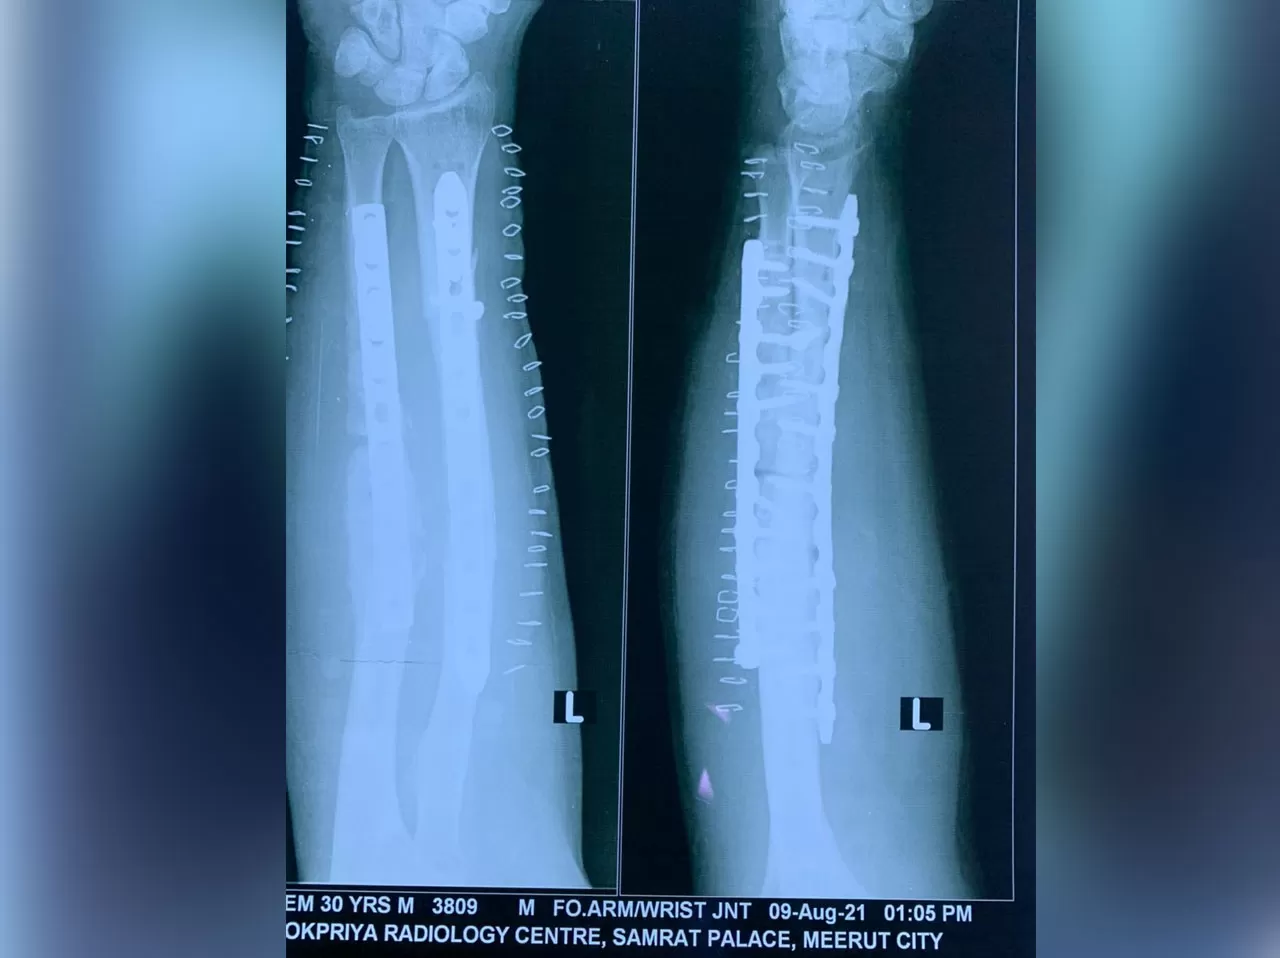

Mr. Naeem

Name: Mr. Naeem

Date of Operation: 5 Aug 2021

Age: 30 Years